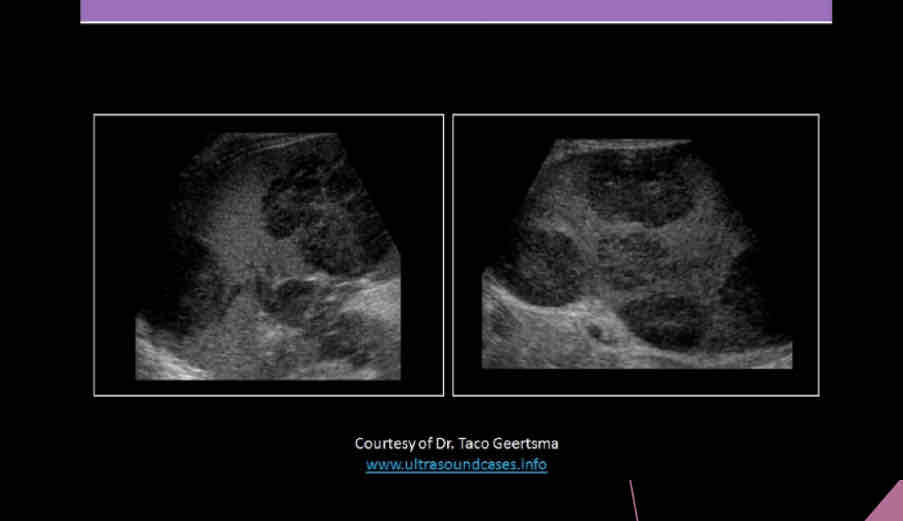

What does the following describe?

•Tumor of lymphatic nodes

•Commonly involves the spleen

•Elevated alkaline phosphatase values

•Solid hypoechoic well circumscribed areas or can be nearly isoechoic

•Marked splenomegaly due to tumor formation

•Areas of cystic degeneration within the tumors

Lymphoma

What are the four sonographic patterns of lymphoma in the spleen?

•Diffuse, marked splenomegaly, patchy inhomogeneity

•Multiple small hypoechoic lesions

•Multiple large lesions

•Bulky solid mass lesions